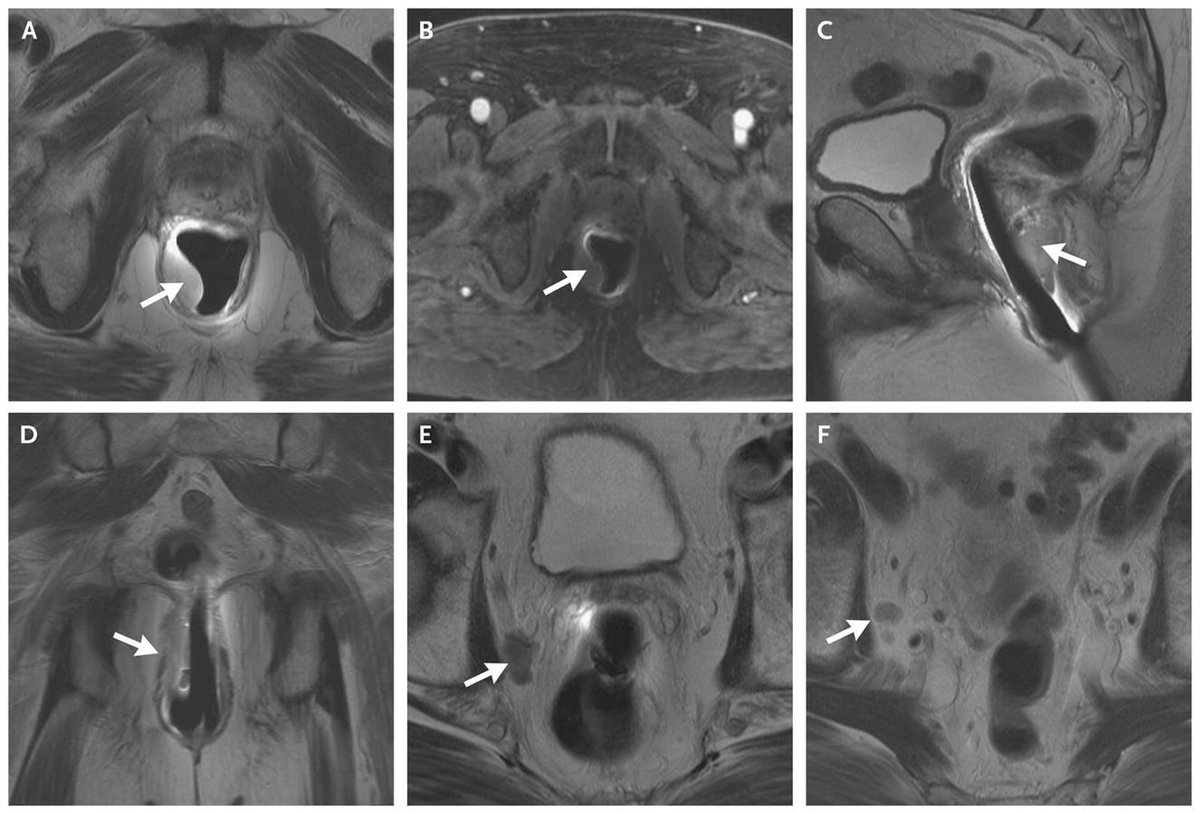

Case Record of the

#MGH: Year-Old Man with Rectal Bleeding and a History of#ProstateCancer http://nej.md/2hamqjr pic.twitter.com/VX3RA4VInT